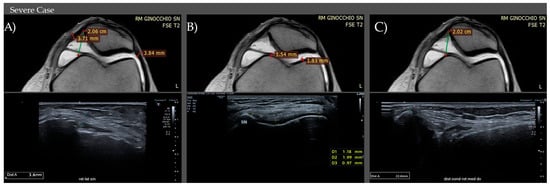

| CONTROLS | Medial Retinaculum | 0.9–1.0 mm (IQR) (M1) | 0.9–1.1 mm (IQR) (M1) |

| Lateral Retinaculum | 0.7–1.0 mm (IQR) (M0.9) | 0.9–1 mm (IQR) (M1) | |

| CASES | Medial Retinaculum | 1.3–2.6 (IQR) (M2.1) Mild: <1.3 mm Moderate: 1.3–2.6 mm Severe: >2.6 mm | 1.5–2.8 (IQR) (M2.3) Mild: <1.5 mm Moderate: 1.5–2.8 mm Severe: >2.8 mm |

| Lateral Retinaculum | 1.2–2.5 (IQR) (M0.9) Mild: <1.2 mm Moderate: 1.2–2.5 mm Severe: >2.5 mm | 1.3–2.5 (IQR) (M2.2) Mild: <1.3 mm Moderate: 1.3–2.5 mm Severe: >2.5 mm | |

| CONTROLS | Medial Thickness | 2.8–4.7 mm (IQR) (M4) | 2.9–4.5 mm (IQR) (M3.8) |

| Lateral Thickness | 3.3–5.1 mm (IQR) (M4.45) | 3.0–4.8 mm (IQR) (M4.2) | |

| CASES | Medial Thickness | 1.5–2.3 (IQR) (M1.8) Mild: >2.3 mm Moderate: 1.5–2.3 mm Severe: <1.5 mm | 1.2–2.1 (IQR) (M1.55) Mild: >2.1 mm Moderate: 1.2–2.1 mm Severe: <1.2 mm |

| Lateral Thickness | 1.8–2.65 (IQR) (M2.3) Mild: >2.6 mm Moderate: 1.8–2.6 mm Severe: <1.8 mm | 1.65–2.5 (IQR) (M2) Mild: >2.5 mm Moderate: 1.6–2.5 mm Severe: <1.6 mm | |